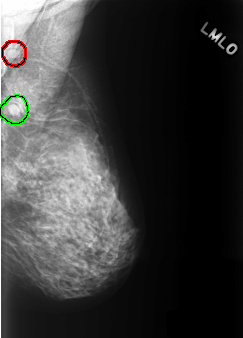

FILE: C_0337_1.LEFT_MLO.OVERLAY

TOTAL_ABNORMALITIES 2

ABNORMALITY 1

LESION_TYPE MASS SHAPE OVAL MARGINS CIRCUMSCRIBED

ASSESSMENT 3

SUBTLETY 5

PATHOLOGY BENIGN

TOTAL_OUTLINES 1

BOUNDARY

ABNORMALITY 2